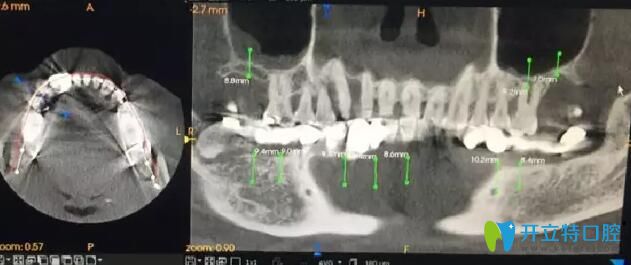

南通摩爾口腔術(shù)前ct

術(shù)前全景片,下頜大部分牙齒缺失,殘留牙牙槽骨吸收明顯,從醫(yī)生的角度看,一個(gè)三十歲左右的青年人,牙病如此嚴(yán)重,實(shí)屬罕見。經(jīng)過了解,王先生從小害怕看牙,有牙齒問題遲遲未做治療,拖延病情至今。本次尋找周院長看牙,一是自己牙齒情況已經(jīng)嚴(yán)重影響到自己的正常生活,二是經(jīng)過多方打聽,相信周院長的技術(shù)一定可以幫助自己擺脫長期缺失牙的狀況。

南通摩爾口腔術(shù)前手術(shù)設(shè)計(jì)

周文清院長根據(jù)王先生的CT判斷,保留33號(hào)、34號(hào)、35號(hào)牙,術(shù)中拔除44號(hào)、42號(hào)、41號(hào)、31號(hào)牙。采用數(shù)字化3D導(dǎo)板導(dǎo)航于32號(hào)、42號(hào)、43號(hào)、45號(hào)、46號(hào)牙位即刻植入5顆ITI種植體。